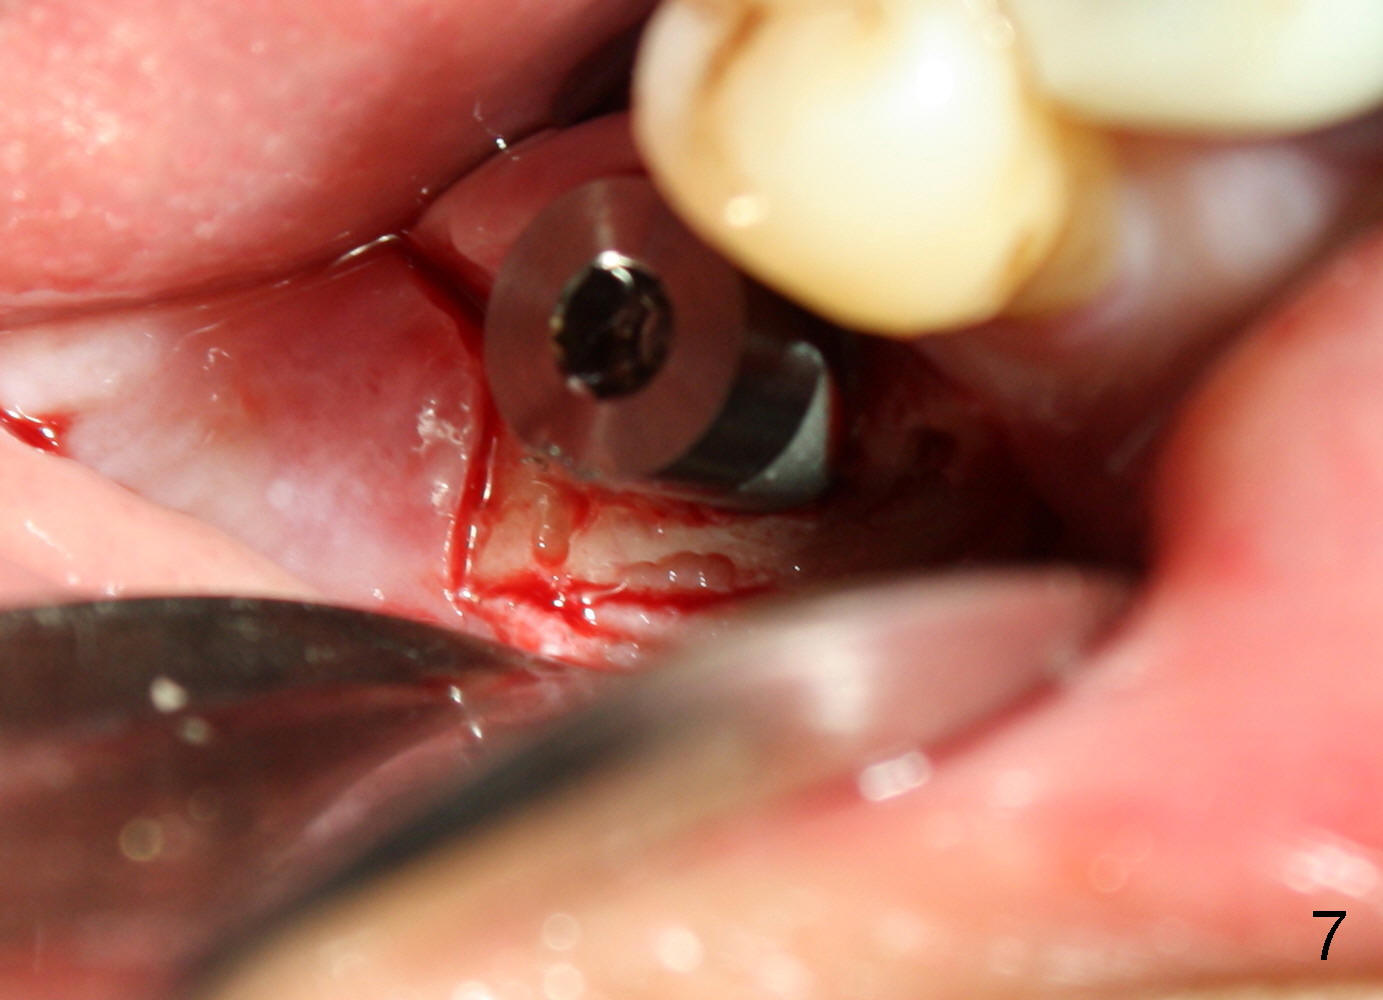

CBCT studies show that a 6x11 mm implant can be safely placed at the site of the tooth #30 (Fig.1 (coronal), 2 (sagittal section). Osteotomy is initiated by 2 mm pilot drill at the depth of 8 mm from the crest (the prospective implant is 3 mm above the crest); X-ray is taken with a parallel pin (Fig.3 P). It appears that there is 12 mm of bone from the crest to the upper border of the inferior alveolar nerve canal. The depth of osteotomy is accordingly adjusted to 11 mm below the crest; osteotomy finishes with insertion of 6x14 mm tap (Fig.4); the patient feels pressure while the tap is being inserted. Following further infiltration with Lidocaine, the depth of the osteotomy is intended to increase in order to bury the implant deeper, because the coronal portion of the buccal plate starts to perforate. The patient feels pain. Finally a 6x14 mm implant is placed ~ 1 mm above the inferior alveolar canal (Fig.5). As mentioned earlier, the rough surface of the implant is exposed buccally (Fig.6 between arrowheads). The nearby buccal plate is decorticated (Fig.7). The autogenous bone harvested during osteotomy (Fig.8) is going to be placed over the exposed portion of the rough surface of the implant (Fig.9); the graft is covered by collagen dressing (Fig.10). The buccal and lingual flaps are approximated with sutures mesial and distal to the implant (Fig.11). To increase the retention of perio dressing, a 4x3 mm abutment is placed.